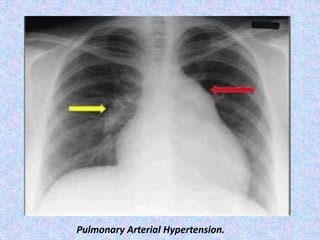

Pulmonary Arterial Hypertension.

Pulmonary hypertension.

Pulmonary hypertension (PH) is an increase of blood pressure in the

pulmonary artery, pulmonary vein, or pulmonary capillaries,

together known as the lung vasculature, leading to shortness of

breath, dizziness, fainting, leg swelling and other symptoms.

Pulmonary hypertension is usually occur secondary to emphysema.

Pulmonary artery dilatation secondary to hypertension.